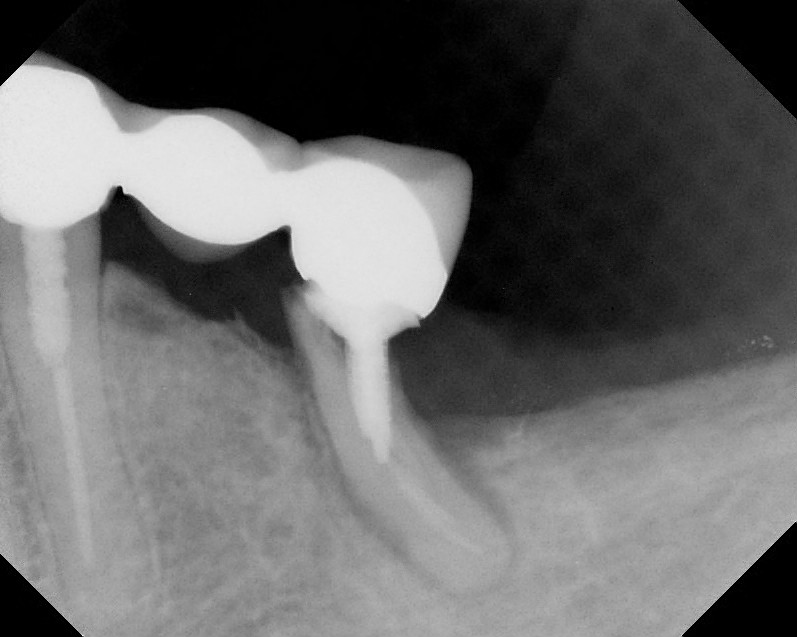

Implants

This treatment involves implanting artificial dental roots, and restoring dental crown without damaging the adjacent teeth.